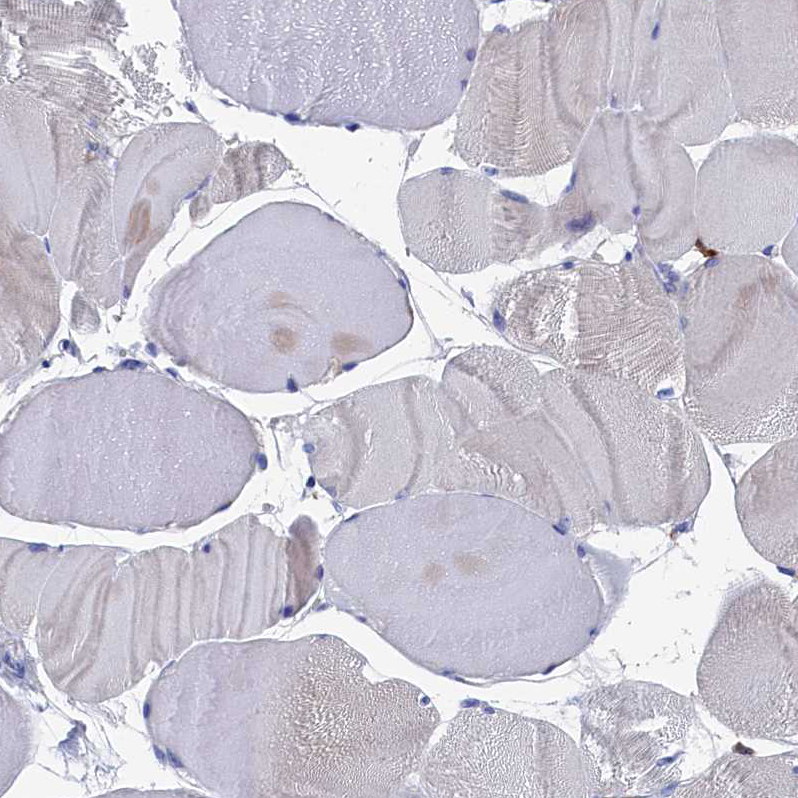

Immunohistochemistry analysis in human bone marrow and skeletal muscle tissues using HPA041899 antibody. Corresponding TYROBP RNA-seq data are presented for the same tissues.